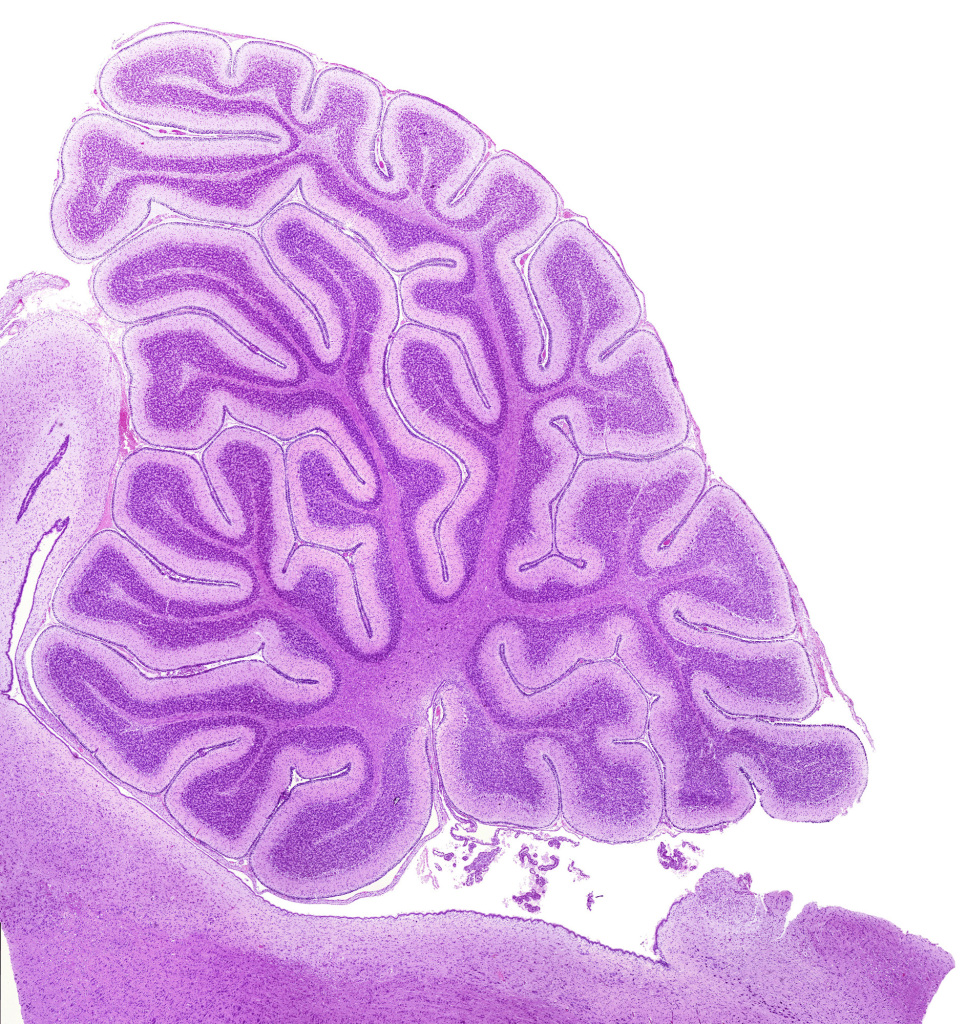

Our medical studies confirmed our interest in histology.